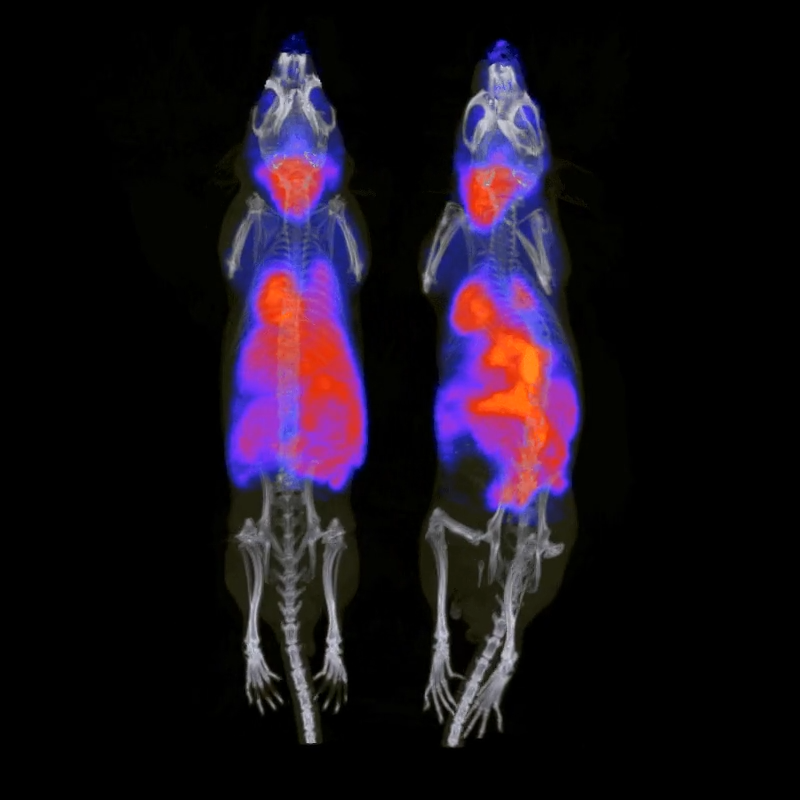

使用¹¹C对小鼠进行短半衰期同位素成像

即使使用短半衰期放射性示踪剂,高计数率耐受性仍支持对多只动物进行定量动态成像。

〉动物:2只,每只20g

〉放射性示踪剂: 每只小鼠注射¹¹C-胆碱,活度分别为5.15 MBq(139 μCi)和5.28 MBq(142 μCi)

〉采集:动态PET成像